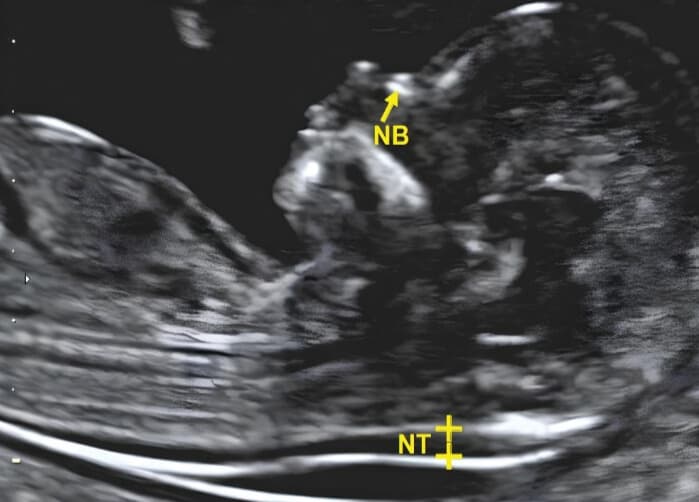

A Nuchal Translucency (NT) scan is a specialized ultrasound examination performed between 11-14 weeks of pregnancy. It measures the fluid collection at the back of the baby's neck to assess the risk of chromosomal abnormalities, particularly Down syndrome and other genetic conditions.

A normal NT measurement is typically less than 3.5mm. However, the interpretation depends on the baby's crown-rump length and is combined with other factors like maternal age and blood test results to calculate the overall risk.